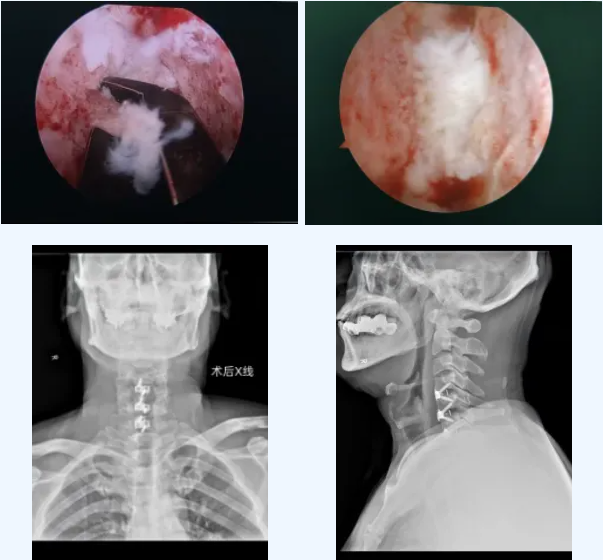

视野放大20倍:4K高清内镜让压迫部位一目了然,实现“可视化”精准操作;

减压更彻底、更安全:可在镜下轻柔、彻底地切除脱出的椎间盘,解除脊髓压迫,极大避免损伤周边神经血管;

保留结构:无需大范围切除椎体,保留了颈椎原有稳定结构;

康复更快:配合使用低剖面内固定,减少术后吞咽不适,特别有利于中老年患者快速恢复。

手术由李主任主刀,顺利清除了致压物,脊髓压迫彻底解除,颈椎稳定性也得到重建。整个过程出血少、创伤小。